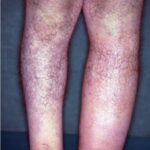

usually begins on the face or a lower extremity, heralded by pain, superficial erythema, and plaque-like edema with a sharply defined margin to normal tissue . These findings are often described as peau d’orange appearance. In the presence of antecedent edema or other anatomic abnormalities, the margin between normal and diseased soft tissue may be obscure, much as in primary cellulitis. There may not be an obvious portal of entry, and skipped areas may confuse the nature of the process. Facial erysipelas is less frequent than lower extremity disease and begins unilaterally but may spread by contiguity over the nasal prominence to involve the face symmetrically . The oropharynx may be a portal of entry, and throat culture may show GAS. Inflammatory edema may extend to the eyelids, but orbital complications are rare. Fever may precede local signs, and, occasionally, before distal extremity

findings, patients complain of groin pain caused by swelling of a femoral node. Lymphangitis and abscess are very rare, but the process may spread rapidly from the initial lesion. Occasionally, in addition to rapid spread of the erythematous, edematous plaque, bullae may form in the involved area.

Recurrent erysipelas is associated with saphenous vein harvest (occasionally in association with tinea pedis) and lymphedema complicating mastectomy with axillary node dissection. In these cases, erysipelas presents with edema and erythema along lines of venectomy or nodal dissection. In addition, resultant lymphedema from a previous episode of erysipelas is a risk factor for recurrence, particularly on the lower extremities. Congenital lymphedema (Milroy disease) may also lead to recurrent erysipelas.